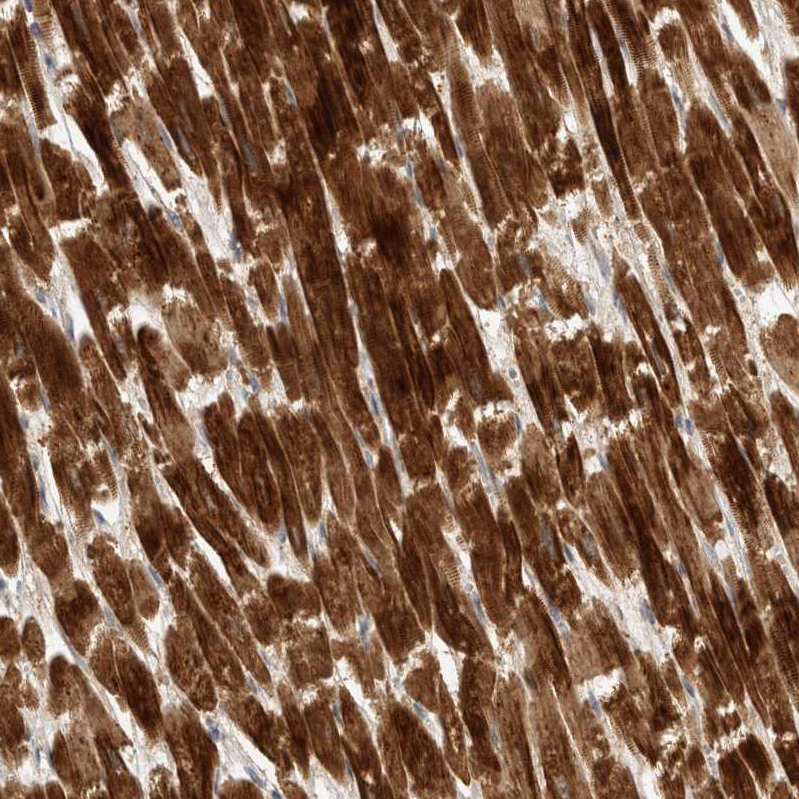

Immunohistochemical staining of human heart muscle shows strong cytoplasmic positivity in cardiomyocytes.